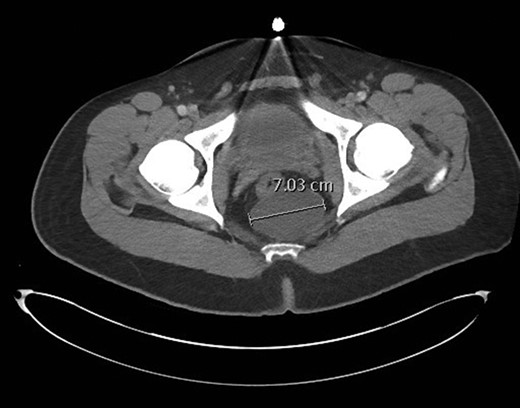

This is a case report describing the resection of a presacral cyst in a 23-year-old male patient. The cyst was discovered incidentally on CT scan of the abdomen and pelvis for evaluation of acute appendicitis (Fig. 1). The patient denied pain, bleeding, or change in bowel habits. He had no neurologic changes. A follow-up MRI was also performed (Fig. 2), and imaging was consistent with a congenital retrorectal cyst, with a tailgut cyst being favored. There was no evidence of bony involvement or invasion of other structures (Figs 1 and 2).

CT pelvis image demonstrating a 7.0 cm retrorectal cyst. The rectum is noted anterior to the cyst, and just to the right of midline.